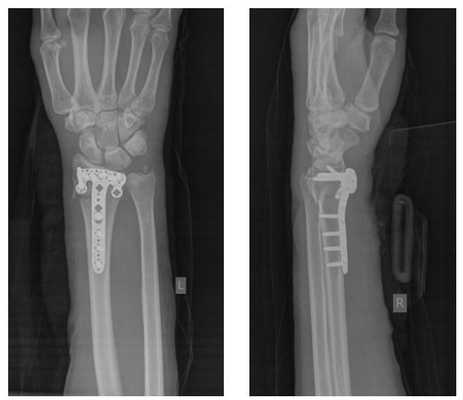

Произведён доступ к месту перелома по ладонной поверхности предплечья. При ревизии выявлено множество мелких осколков в метафизарной области по волярному кортексу. Произведена открытая репозиция перелома, временная фиксация спицами. Накостно уложена пластина VA-LCP™ Two-Column Distal Radius Plate

После рентгенконтроля производится введение блокируемых винтов диаметром 2,4 или 2,7 мм.

Данная пластина отлично подходит для фиксации оскольчатых переломов дистального метаэпифиза лучевой кости, однако в ряде случаев, когда перелом располагается более дистально, предпочтительнее использовать пластину другой конструкции (Volar rim).

Окончательный остеосинтез после проведения всех винтов выглядит на рентгенограмме примерно так. На левой части рисунка схематично отображено расположение фрагментов кости, фиксированных пластиной.

Например у Пациентки А, 24 лет, операция выполнена по поводу относительно простого перелома дистального метаэпифиза лучевой кости с угловым смещением к тылу на 30 градусов и укорочением лучевой кости на 7 мм. Учитывая молодой возраст и высокие функциональные запросы принято решение о выполнении остеосинтеза. Учитывая сохранность волярного кортекса использована пластина меньшего размера, которая установлена более проксимально, с целью максимального сохранения кровоснабжения эпифиза лучевой кости.

Через 6 недель наблюдается рентгенологическое сращение перелома. Функция конечности к этому времени уже практически полностью восстановлена.